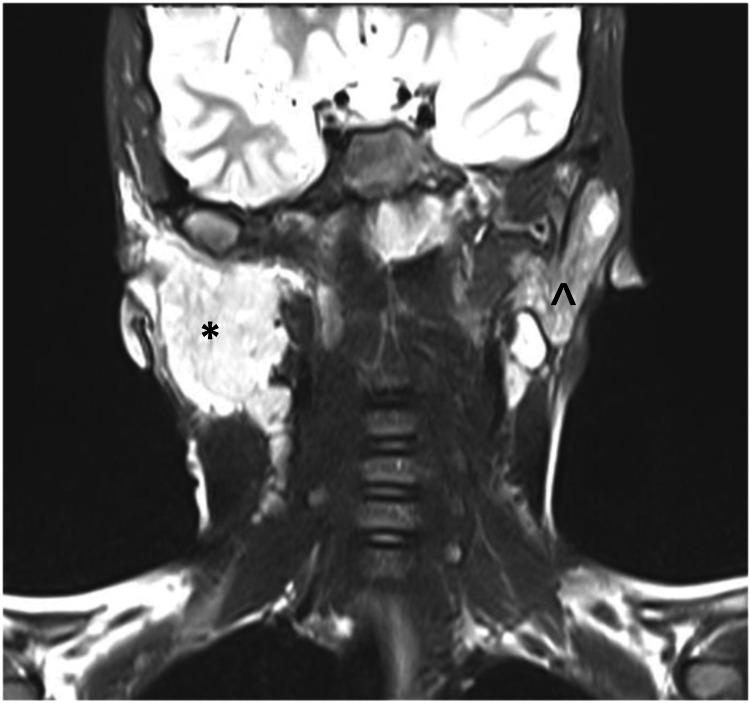

Juvenile recurrent parotitis (JRP) is a rare recurrent non-obstructive inflammatory swelling of the parotid gland occurring most commonly in children aged three to six years. JRP is usually idiopathic and presents as a painful swelling recurring on either side of the face at least twice within six months. We report the case of an eight-year-old Saudi boy with a painful acute right-sided parotid swelling and a history of similar occurrences bilaterally at least four times a year for two years. The routine laboratory investigations were unremarkable. Ultrasonography of the parotid glands suggested parotitis with cervical lymphadenopathy. He was treated conservatively and remained asymptomatic for a year. Although rare, an accurate diagnosis of JRP is possible with adequate history, physical examination, and lab investigations, supplemented with radiographic findings.

青少年复发性腮腺炎(JRP)是一种罕见的、复发性的、非阻塞性腮腺炎性肿胀,最常见于3至6岁的儿童。JRP通常为特发性,表现为面部两侧至少在6个月内复发两次的疼痛性肿胀。我们报告一例8岁沙特男孩,其右侧腮腺出现疼痛性急性肿胀,且有两年间每年至少双侧类似发作4次的病史。常规实验室检查无异常。腮腺超声检查提示腮腺炎伴颈部淋巴结病。他接受了保守治疗,一年内无症状。尽管罕见,但通过详细的病史、体格检查、实验室检查,并辅以影像学检查结果,有可能准确诊断JRP。